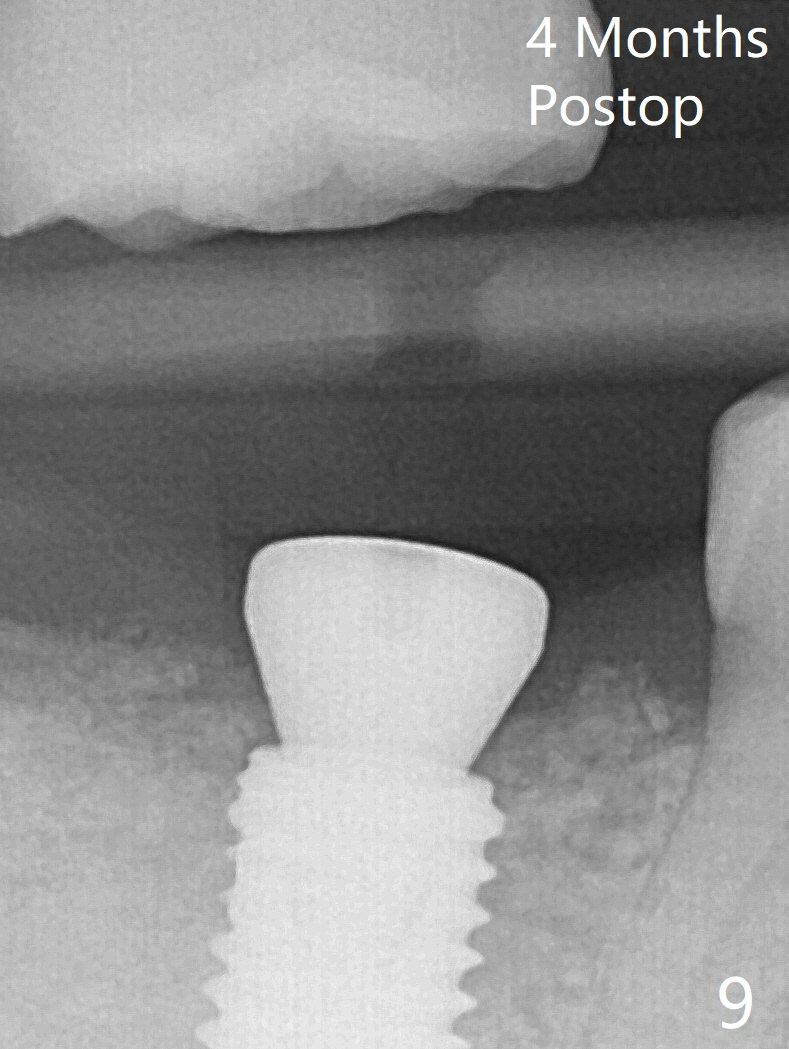

CBCT shows thin cortical bone formation mesiodistally 6.5 months post socket preservation with allograft with PRF at #31 (Fig.3 ^, as compared to Fig.1). The socket appears to be closing buccolingually 10 months postop (Fig.6 arrowheads, as compared to Fig.4). Bone density increases from 1100 units to 1,200-1,400 units 6.5 to 10 months. With underprep (4 mm), a 5x10 mm implant is placed with ~ 50 Ncm with guide (Fig.7). Following a 5.5 mm profile drill, a 5.5x3 mm healing abutment is placed (Fig.8); the implant plateau appears to be supported by the graft bone (*). The implant remains subcrestal 4 months postop (Fig.9).